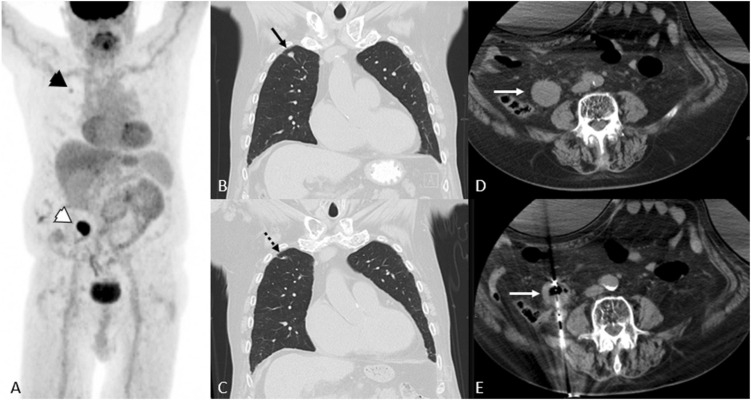

Imaging response assessment figureImaging response assessment for oncology: An algorithmic approach

Kathleen Ruchalskia, Rohit Dewana, Victor Saia, Lacey J.McIntosh, MartaBraschi-Amirfarzanc. Dr. Lacey McIntosh co-authored a paper with other cancer imagers from UCLA and Lahey/Tufts on an algorithmic approach for imaging response assessment in oncology patients that was just published in the European Journal of Radiology Open!

Imaging response assessment for oncology: An algorithmic approach

June 07, 2022. Author(s): Kathleen Ruchalski, Rohit Dewan, Victor Sai, Lacey J. McIntosh, Marta Braschi-Amirfarzan. Source: European journal of radiology open